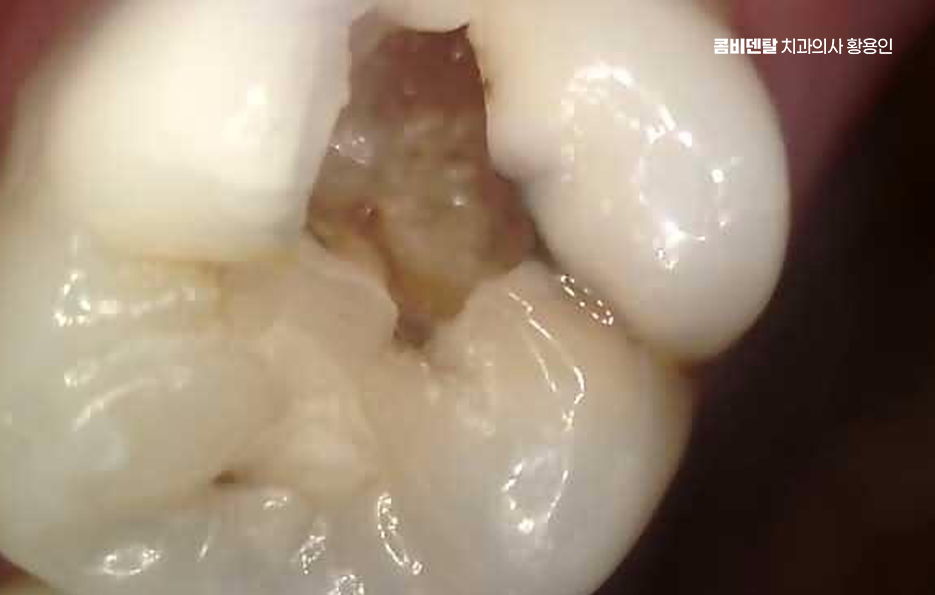

신경치료 아픈가요 우선 치료 과정에 대해 좀더 이해해보면 신경치료는 단계적으로 진행되는데 첫 번째는 염증이 생긴 신경을 제거하고, 치아 내부인 근관을 깨끗하게 소독하는 과정으로 이때 통증이 가장 예민하게 느껴질 수 있는 구간인데, 이를 줄이기 위해 국소마취를 정밀하게 시행하고 있어요

이미 신경이 괴사한 경우엔 오히려 통증이 전혀 없는 경우도 있으며 마취가 충분히 이루어지면 미세한 기구로 치아 내부를 조금씩 넓혀서 염증 조직을 제거하고, 감염된 부분을 없애게 되는데 이 과정에서 드릴 소리나 압력감이 불편하게 느껴질 수 있어요.

이 과정에서 중요한 건 근관 내부를 완전히 소독한 후, 안쪽에 약재를 채워서 다시 세균이 침투하지 않게 밀봉하는 거예요. 이걸 제대로 하지 않으면 시간이 지나면서 2차 감염이 생기고, 다시 신경치료를 해야 하거나, 결국 발치까지 가게 되는 경우도 있어서, 처음 치료가 정밀하게 이뤄지는 게 무엇보다 중요하며 근관치료가 완료되면 그 위에 보강재를 넣고, 크라운을 씌워 치아를 보호하게 되는데 신경을 제거한 치아는 수분과 영양 공급이 끊어져서 점점 약해지고 깨지기 쉬워지기 때문에 신경치료 후에는 크라운을 씌우는 것이 수순이라 할 수 있어요